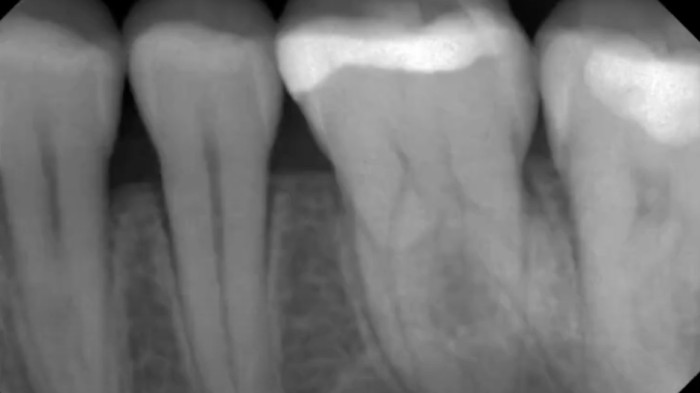

Near-infrared transillumination empowers clinicians to detect proximal lesions that might escape clinical observation and distinguish between lesions confined to the enamel and those that have progressed to the enamel-dentin junction.

Interproximal caries

X-Ray

“It is the best method of caries diagnosis, and you can use it safely. […] [regarding] class II cavities and non-cavitated approximal caries, DIAGNOcam has better sensitivity and specificity than bite-wing x-rays [… ] cavity shape is much better explained and visible.”

— Mikolajczyk M. (2024)